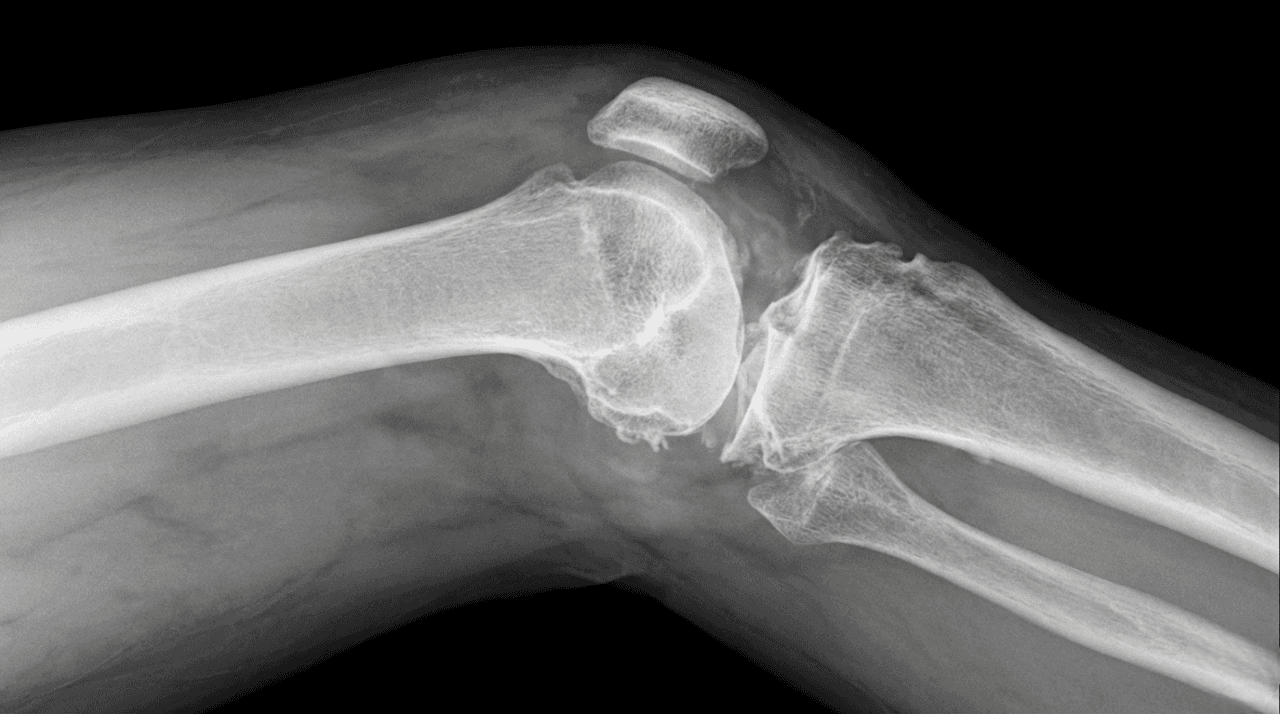

As a distinguished knee specialist in Dubai, Dr. Farid Ghasemzadeh Mojaveri is trusted by patients for complex joint reconstruction and trauma care. The knee's intricate anatomy makes it susceptible to acute sports injuries and long-term wear. As a dedicated knee surgeon in Dubai, Dr. Farid emphasizes precise diagnosis, ensuring that whether you need conservative knee pain treatment or a definitive surgical solution, your plan is tailored for optimal functional recovery.

Expert Diagnosis and Treatment for Knee Conditions

Arthritis & Cartilage: We provide comprehensive osteoarthritis knee treatment options, ranging from joint preservation, like articular cartilage surgery, to definitive solutions, such as advanced knee replacement surgery in Dubai.